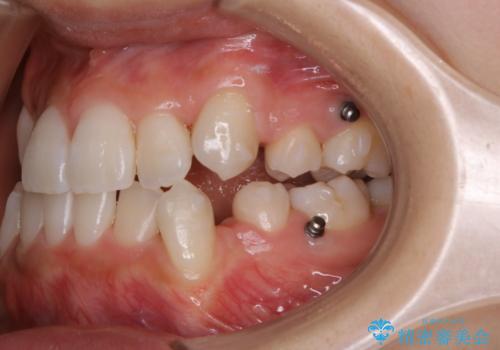

- インビザラインでのマウスピース矯正中に着色が気になるとのことでした。着色が全体的に付着していたためPMTC60分コースを行いました。

PMTC(保険外治療)は、毎日の歯磨きで落としきれない汚れや、コーヒ、紅茶・タバコのヤニなどの着色も除去します。目には見えない歯と歯の間・歯肉の境目・インビザライン中はアタッチメント周囲などに残っているプラーク(歯垢)もしっかり取り除きます。PMTCでは専門的な機械や材料を使用して、徹底的に汚れを除去するため、虫歯・歯周病・口臭予防などにつながります。